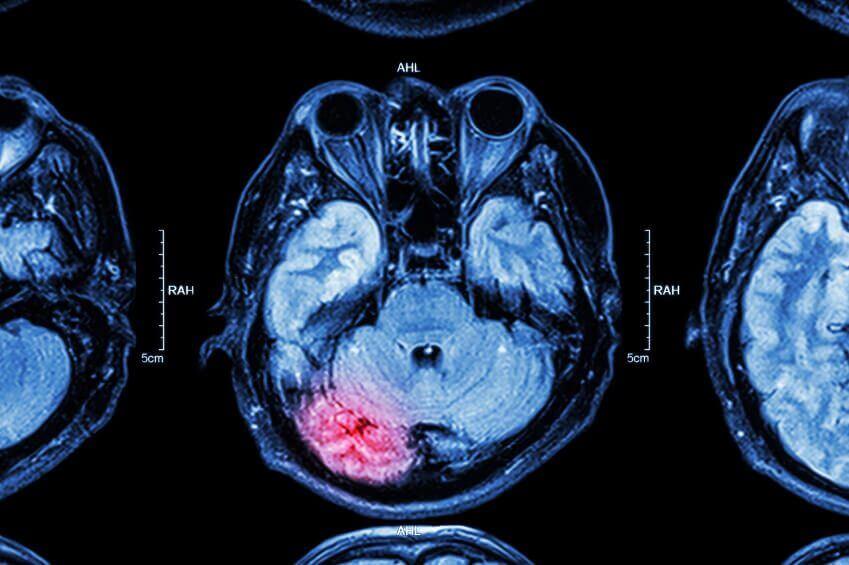

Medical Innovations: Research Breakthrough to Revolutionize Stroke Treatment

A recent article from ‘The Heart and Stroke’ reports on the dramatic results from a new clinical trial which are set to change the way many strokes are treated in Canada and around the world. A new treatment was shown to cut in half the death rate from major ischemic strokes in the ESCAPE trial.